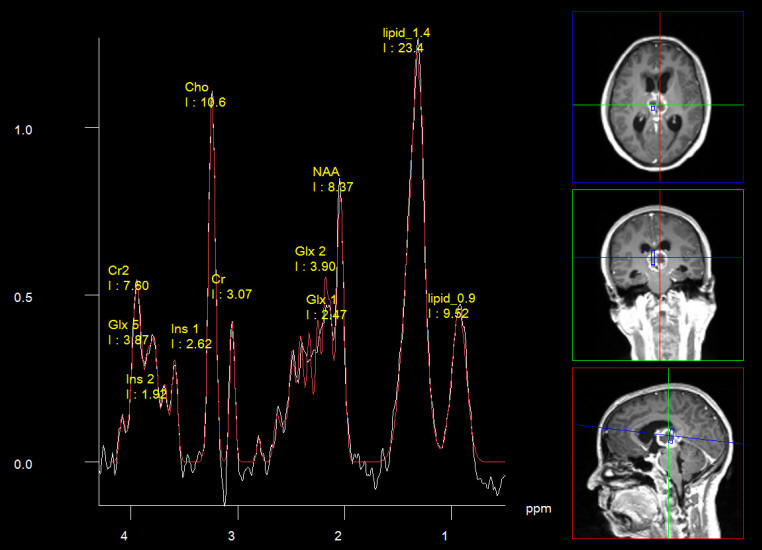

Among the MRI neuro clinical applications, MRI spectroscopy 15 is the most important one in presence of brain masses. It can with confidence tell if the lesion is an abscess, lymphoma, active multiple sclerosis lesion, grade of malignancy of the brain tumors.12 It is useful tool before surgery, that when the patient coming with report as having brain tumor, to end with an abscess. It is useful even during surgery to differentiate the tumor residual from hematoma due to surgical intervention. Even with strict hemostasis, when you send the patient to the MRI some amount of hematoma accumulate, and SWI and spectroscopy can help in the nature of the residual.

Below, showing a case with posterior third ventricular anaplastic ganglioma in 30 years old patient to whom intraoperative MRI with spectroscopy, SWI and MRA were performed twice to confirm the total resection of the tumor. See fig-1-7.

Fig-2: Short Echo spectroscopy in favor of pinealoblastoma, which proved later to be anaplastic ganglioglioma. These data before attacking the lesion.

Fig-6: Spectroscopy short TE showing low choline ratio? with high lipids 1.3 and 0.9. confirming resection of the residual